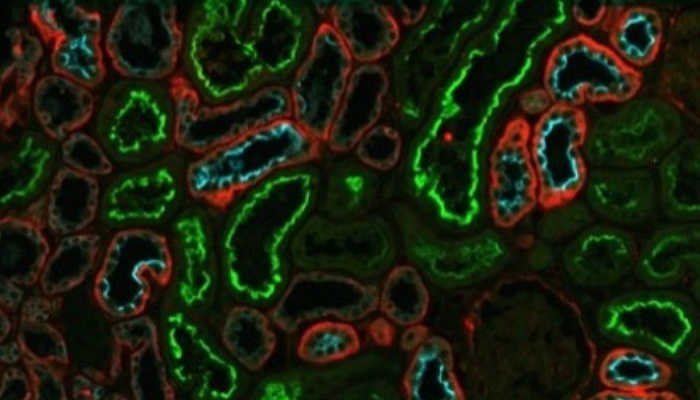

Флуоресцентная микроскопия клеточного деления